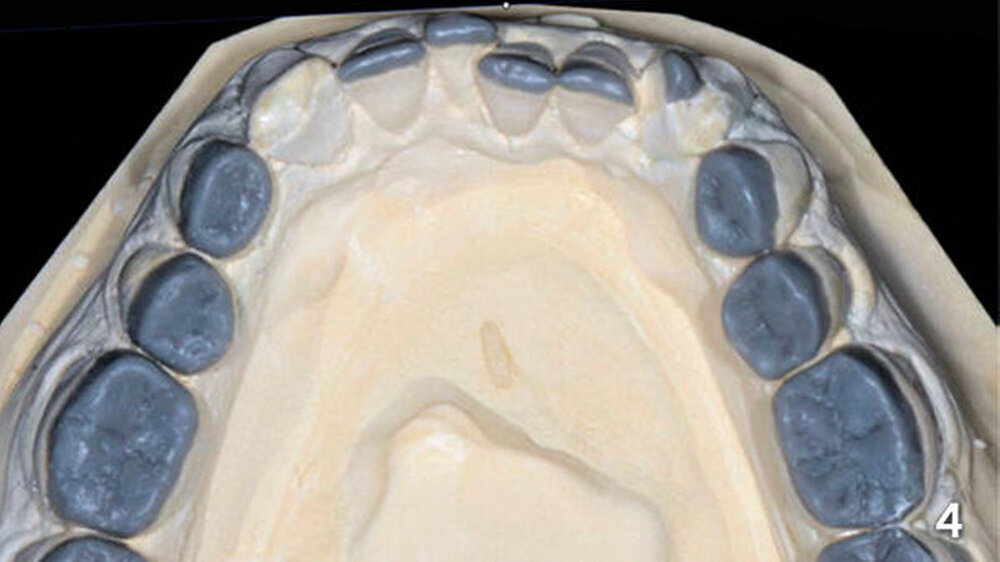

Bei der Anfertigung der Wax-up-Modelle wurden jeweils die Eckzähne und Bereiche der endständigen Molaren nicht mit Wachs aufgebaut (Abb. 4). Auf den Modellen wurden dann für den Unterkiefer je zwei stabile, lichtdurchlässige Übertragungsschienen hergestellt, die später im Mund eine ausreichende Abstützung an den nicht aufgewachsten Eckzähnen und den distalen Bereichen der endständigen Molaren gewährleisteten (Abb. 5).